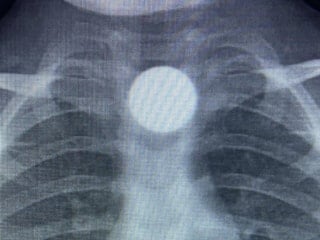

Kavgada Adem Ünver, Ahmet Kalkancı’yı karnından, Halil Can Kalkancı’yı ise sol bacağından vurdu. Mermiler, çevredeki iş yerleri ile 2 otomobile de isabet etti.